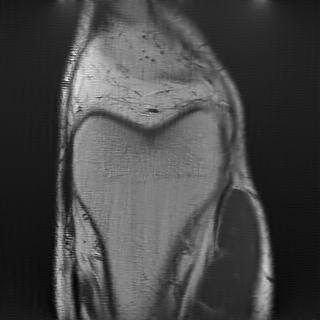

In our experiments, we consider a subsampling ratio of and , meaning that or respectively. The parameter encodes all the parameters above. The sensitivity maps and the trajectory perturbations are usually unknown, making MRI reconstruction a blind inverse problem. Examples of realistic sampling trajectories used in this work are displayed in Fig. 2, bottom.

The training database is the fastMRI knee training dataset [95]. It contains images of size . All evaluations were performed on the validation set of the fastMRI knee database containing 2D slices. We used the efficient cuFINUFFT transform [80], which is the fastest available library in our experiments (see https://github.com/albangossard/Bindings-NUFFT-pytorch for comparisons).

For MRI reconstruction, we considered measurements coming from a single reception coil, to reduce the computational complexity. We used both the denoising network and the unrolled proximal gradient descent on different schemes: a radial one (, Fig. 2(a)), a horizontal one (, Fig. 2(b)) and a vertical one (, Fig. 2(c)). In addition, we used two crosses, which do not belong to the training family . The first one is aligned with the axes (, Fig. 2(f)) and the other one with the diagonals (, Fig. 2(g)).

6.3.1 Magnetic Resonance Imaging

This application provides surprisingly good results for various reasons:

To the best of our knowledge, no one yet attempted to estimate the sensitivity maps and trajectory errors jointly. Estimating divergence in trajectories might look hopeless at first sight, which may explain this fact. Indeed, looking at the differences between and (see top-right and the zoom on the right-most column of Fig. 5) we see that the frequency shifts are huge (up to 5 pixels).

-

•

The total number of parameters to estimate is large. Indeed, it consists in the parameters describing the sensitivity maps and the parameters describing the convolution kernel that perturbs the trajectories, i.e. parameters.

If solved without any correction, the reconstruction results are disastrous (see the 2nd column). Solving the consistency problem (5) provides near perfect estimates of for all reconstruction mappings. For instance, the green and orange trajectories cannot be distinguished on the right column. This may come as a surprise, and seems to suggest that this particular blind inverse problem is not as hard as it may seem at first sight. This might be due to some redundancy in the data: the reception coils associated to a slight oversampling of the -space center (all the trajectories start exactly from the center) seem to ensure the identifiability of the problem. A nice research perspective is to explain this phenomenon from a theoretical viewpoint.

The reconstruction result obtained with the neural network trained on a family is significantly better than the two other ones (more than dB compared to the one trained on and to the P&P approach). In particular, the bone texture is reconstructed with the proposed approach, while it is not for the two others.

To further validate the method, we tested the methodology on 9 additional images. The results are reported in Table 3. As can be seen, the method recovers good estimates of the sensitivity maps and trajectories in all cases. This results in a huge PSNR increase, since the forward model is essentially correct after estimation.